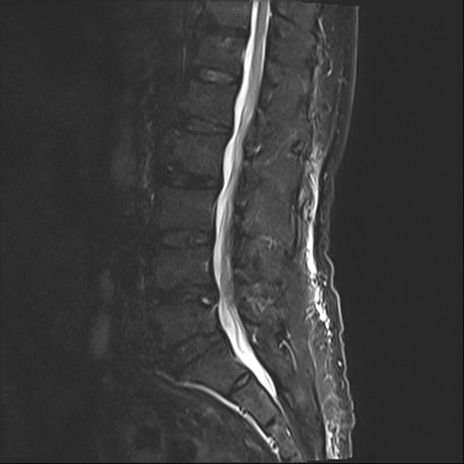

【整形】TIPS症例2 腰椎MRI STIR(矢状断像)

【症例】70歳代男性

【主訴】左下肢痛

【現病歴】2週間前くらいから腰痛、左下肢痛あり。左臀部から大腿、下腿外側のしびれが常時ある。歩行とともに同部位の痛みあり。

【身体所見】Lasegue70-/60+、Bragard-/±、PTR ±/±、ATR -/-、IP 5/5、TA 5/4、TS 5/5、EHL 右第1足趾なし/3、FHL 5/5、hypersthesia(-)、足背動脈触知良好

異常所見と診断は?